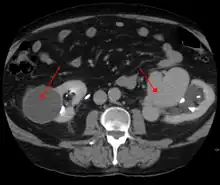

An arterial venous malformation of the left kidney and a simple cyst of the right kidney

An arterial venous malformation of the left kidney leading to aneurysmal dilatation of the left renal vein and inferior vena cava